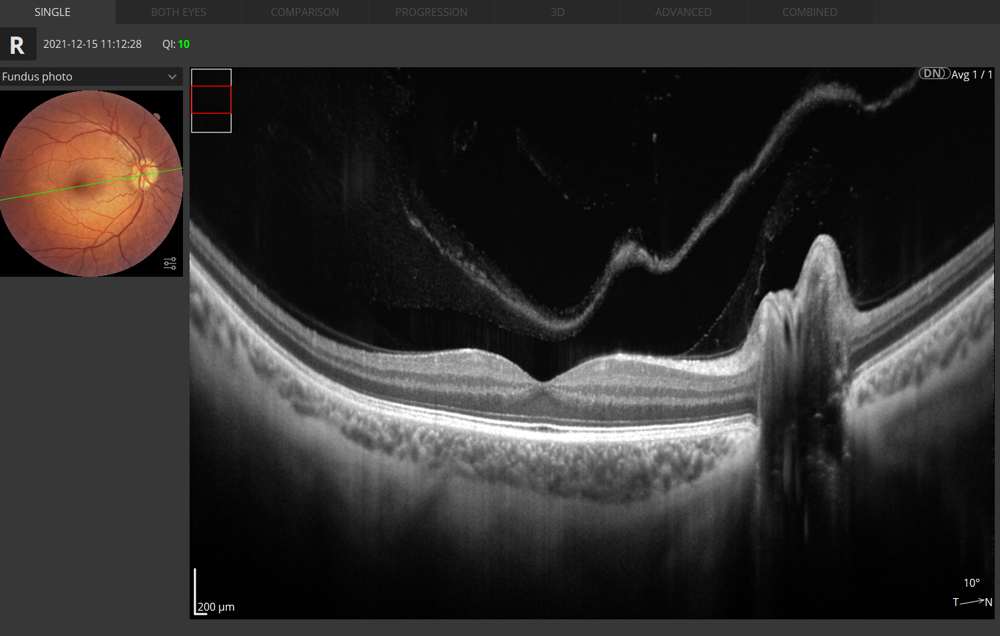

Retina 3D Les deux yeux

Retina B-scan Vue unique